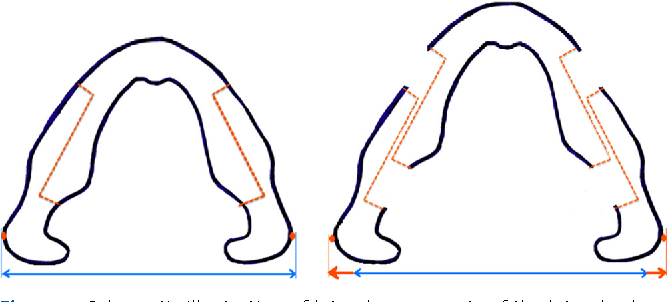

https://www.semanticscholar.org/pap...ahon/7ba8b84eeef2c292ef09a21455a049333d5559b7

Also mandible looks much more squarer